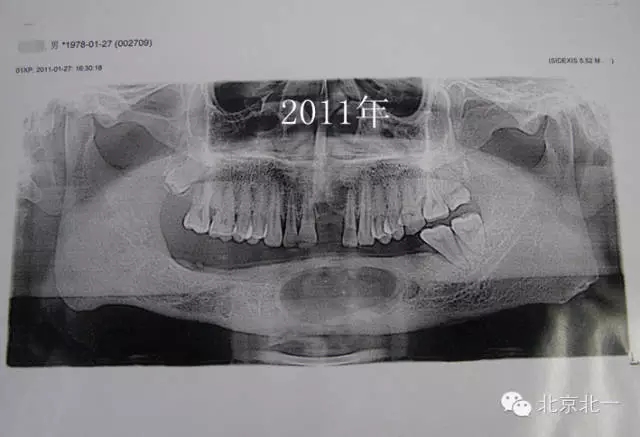

圖三、再次手術后第二次復發(fā)

640 (2).webp (2).jpg